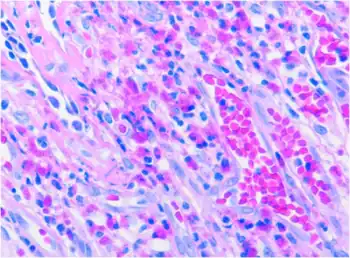

Lung showed inflammation with eosinophilic infiltration, without vasculitis